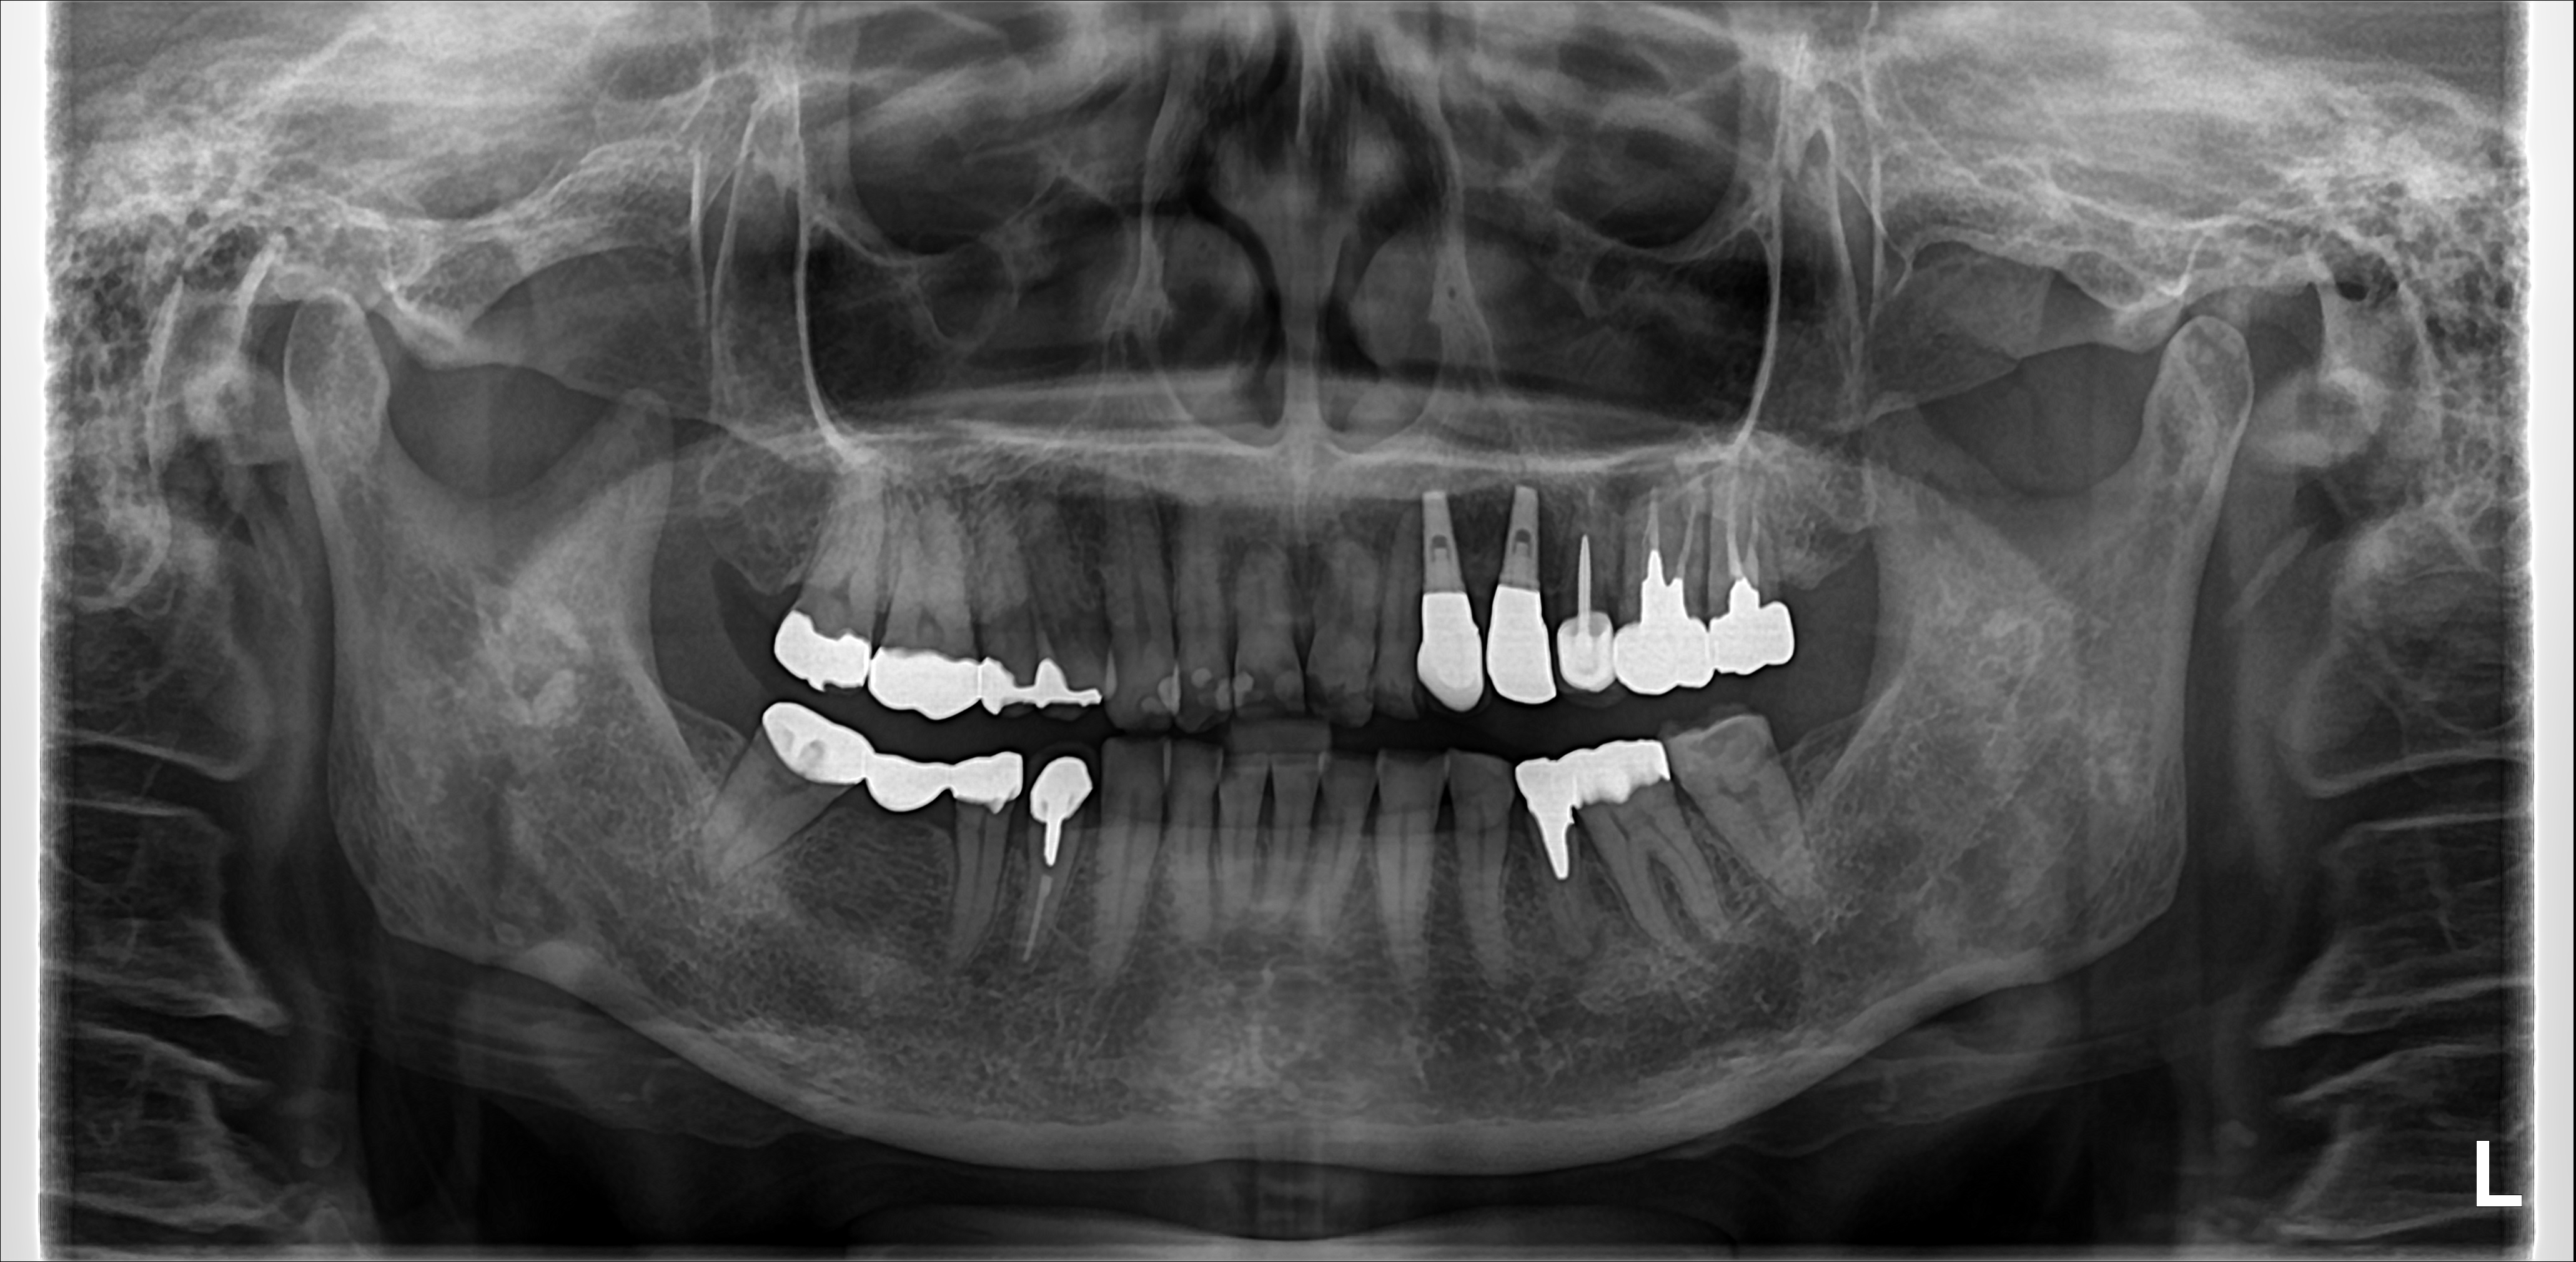

歯ぎしりのある患者にインプラントをして14年経過

この患者さんは歯ぎしりが原因で上顎左側3,4番を欠損となり、そこにインプラント入れました。就寝時はナイトガードの使用が必要となります。

この症例ではインプラントを埋入して14年経過しています。使用したインプラントは今は販売していないエンドポアインプラントです。エンドポアインプラントも成績が良く、これがなぜ製造中止になったか全く理解できない製品です。この件は以前ブログで書いているとおり、某大手メーカーの製品よりはるかに性能が良いです。

この症例では治療費は1本273000円(税込み)で治療しています。20年経過も十分可能だと思います。